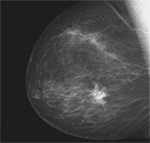

La mamografia digital redueix els resultats falsos positius en la detecció precoç de càncer de mama

L'ús d'aquesta tecnologia disminueix els efectes adversos de la mamografia de cribratge, ja que evita que moltes dones se sotmetin a noves proves diagnòstiques innecessàries, algunes invasives com les biòpsies

Aquesta investigació, publicada a la revista Radiology, contrasta l'eficàcia de la mamografia digital (MD) vers la mamografia convencional i demostra que quan hi ha un tumor ambdues proves el detecten per igual, però en casos en què la imatge pot semblar un càncer sense ser-ho, l’MD afina més el diagnòstic i redueix així els resultats falsament positius, en conseqüència, l’angoixa de les dones en no necessitar fer-se altres proves com ecografies o biòpsies alhora que fa més eficients els programes de cribratge de càncer de mama en disminuir la despesa.

Mamografia digital versus analògica

La investigació, liderada per la doctora Maria Sala de l'Hospital del Mar i coordinadora del grup de recerca en epidemiologia i evaluació de l'IMIM, s'ha desenvolupat a partir de l'anàlisi d'un total de 242.838 mamografies de cribratge (171.191 per tècnica analògica; 71.647 per mètode digital) de quatre programes de detecció precoç de càncer de mama de Barcelona, Girona, València i Cantàbria. A l'examen, realitzat entre 1996 i 2007, hi ha participat un total de 103.613 dones d'entre 45 i 69 anys. “En total, s'han diagnosticat 1.080 càncers sense diferències significatives entre mamografia analògica i digital, però hem observat que el percentatge de proves innecessàries ha estat inferior amb l’MD”, assenyala la investigadora Maria Sala. Aquestes conclusions deriven d’un projecte molt més ampli i multicèntric, coordinat des de l’Hospital del Mar pel Dr. Xavier Castells, Cap del Servei d’Epidemiologia ,on hi participen els Programes de cribratge més consolidats de l’Estat espanyol.